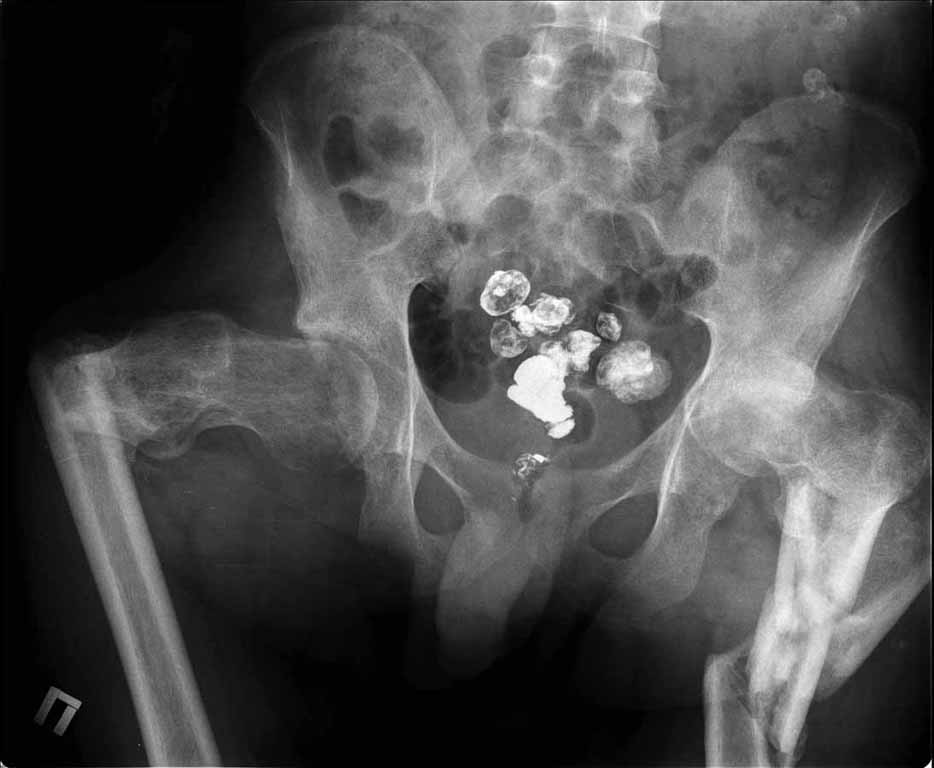

Пациенту 22 года. Травма в июле 2010г, лечился в районной больнице. К нам попал в апреле 2011г.Тяжелая сочетанная травма (29.07.2010): тупая травма живота с повреждением внутренних органов. Закрытая травма грудной клетки с переломом ребер. Пневмоторакс справа. Тяжёлая позвоночно-спинномозговая травма. Закрытый осложнённый переломо-вывих С5 позвонка. Верхний парапарез, нижняя параплегия, нарушение функции тазовых органов по типу недержания. Цекостома. Пролежень левой ягодичной области. Неправильно консолидированные переломы верхних третей обеих бедер. Застарелый вывих левого бедра.Осложнение: Поддиафрагамльный абсесс слева, забрюшинного пространства. Свищ желудка и ободочной кишки. Синегнойный сепсис. Двухстороняя пневмония. Но это уже анамнез.Пациент был неоднократно оперирован на органах брюшной полости и осложнениями с ними связанными.

В ягодичной области слева глубокий пролежень размером 2х2см, дном является вывихнутая головка бедра. Неврологически в нижних конечностях динамика положительная, появились движения в правой стопе, чувствительность в стопах.По переломам бедер: подвижности в местах переломов нет, снимки высылаю.

Уважаемые коллеги, помогите определиться с оптимальной тактикой в лечении перелома бедер. Степень оснащенности у нас достаточная (аппараты, штифты, пластины, ЭОП).

Планирую начать с правого бедра, ЧКО таза (передняя рама) с фиксацией бедра. О/клазия места перелома правого бедра и устранение грубых смещений в аппарате. окончательно можно оставить и в аппарате. Далее аппаратное устранение вывиха левого бедра.